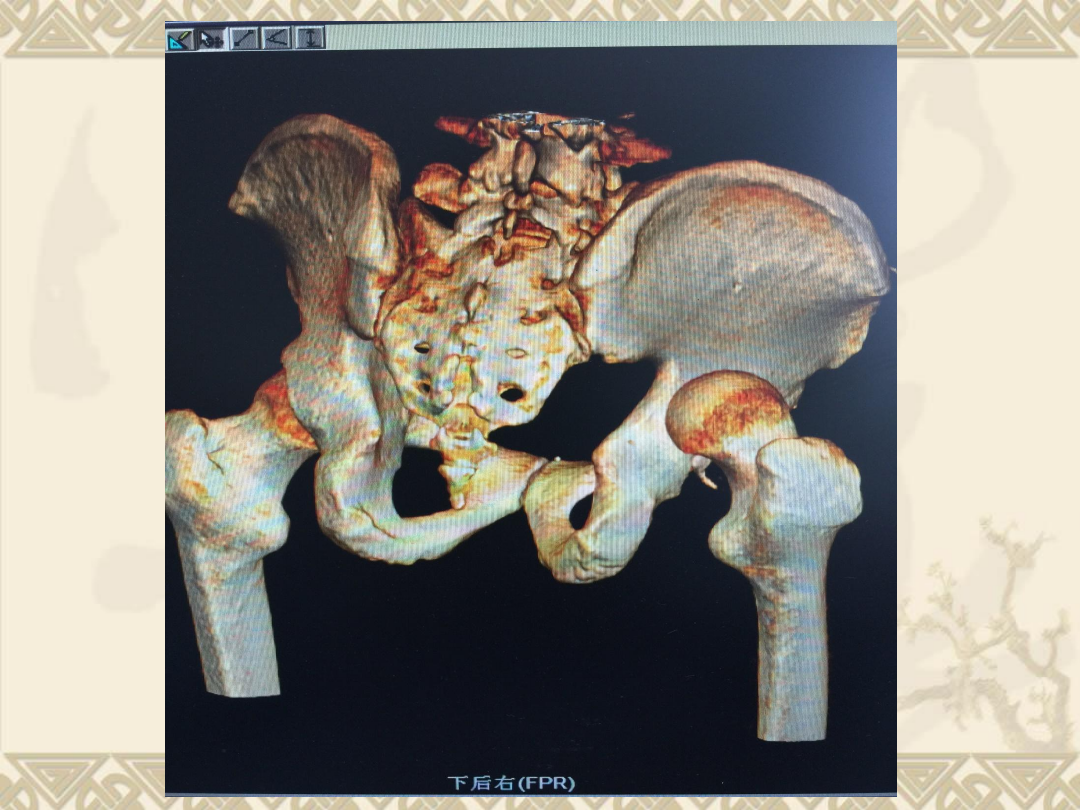

股骨头骨折合并髋关节脱位

及髋臼后缘骨折

v

1

、右股骨头骨折(

Pipkin

Ⅳ型骨折)

2

、髋关节后脱位

3

、髋臼后缘骨折